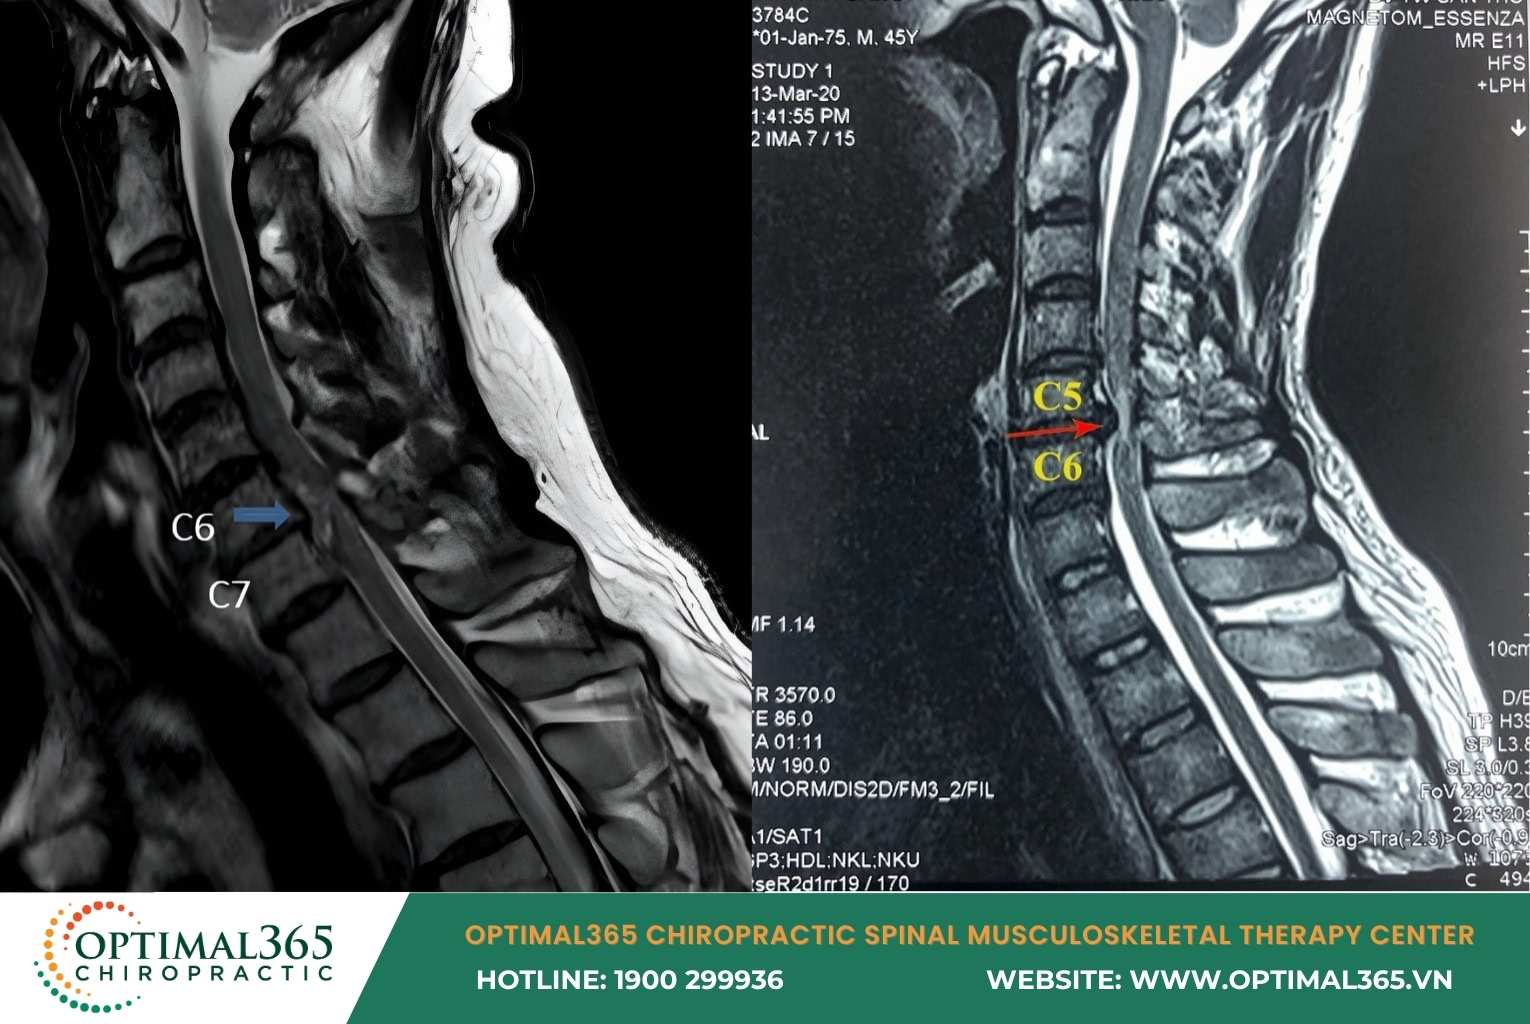

In subclinical cases, cervical herniated disc symptoms are detected via MRI showing: Disc herniating anteriorly or posteriorly, nucleus pulposus displaced, spinal structure changes, and compression on nerve roots or spinal cord.

The cervical spine consists of 7 vertebrae: C1, C2, C3, C4, C5, C6, C7, connected by intervertebral discs, slightly curved in a C-shape. Each disc acts like a “rubber cushion” with a jelly-like nucleus pulposus in the center and a fibrous annulus outside, absorbing shocks and enabling spinal flexibility.

Cervical herniated disc happens when the disc ages, tears, or suffers trauma. At this point, the nucleus pulposus protrudes from the annulus, compressing nerve roots or the spinal cord, causing pain and various symptoms.